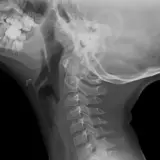

Over 2,100 interactive radiology cases, curated by radiologists for your level of training. Scroll, window, and view cases full screen โ€” just like on PACS. Click linked findings in each writeup to jump straight to them on the image. Cases include sample reports, a focused discussion section, original illustrations, and videos.

Casi completamente interattivi con gli strumenti che ti aspetti su un PACS: scroll, windowing, zoom, pan, misurazioni, ROI e modalitร  a schermo intero.

Annotazioni dettagliate evidenziano i reperti chiave direttamente sui casi. Clicca sui reperti collegati nella descrizione del caso per saltare alla loro esatta posizione sullo scan.